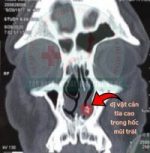

Đọc thêm >>Vừa qua, bệnh viện Tai Mũi Họng TPHCM đã can thiệp thành công lấy mảnh xương cá ra khỏi hốc mũi của người bệnh đã bị bỏ quên suốt gần 3 năm. Bệnh nhân T.V.C (47 tuổi, Cà Mau) cho biết: “tôi bị nghẹt mũi trái tái đi tái lại thường xuyên khoảng 3 năm […]